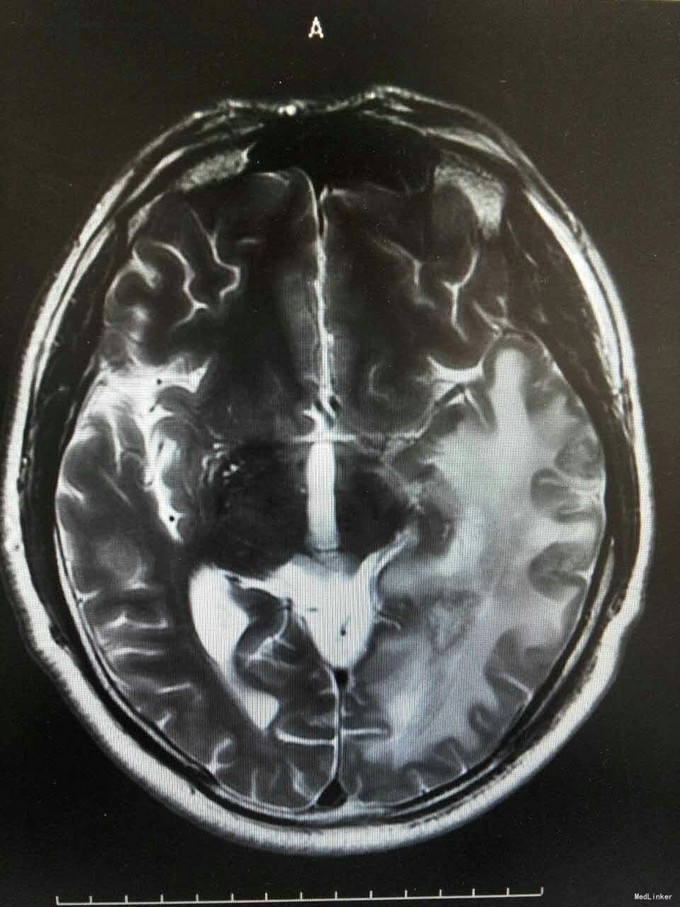

患者姜磊,男,49岁,主因"发作性视野缺损、失认8年余"于2015-11-20再次入我院,患者缘于8年前无诱因出现发作性视野缺损,伴阅读能力、理解力、认知能力下降,每次发作症状持续约3-5分钟左右,可自行缓解,无意识丧失、视物旋转、言语不利,无肢体活动障碍、大小便失禁。入院复查头颅MRI平扫+增强示:原左侧小脑幕、颞叶炎症治疗后,与2014-09-10日片比,病灶较前增多、增大。8年来间断在我院以:颅内非特异性炎症、症状性癫痫、高血压病 住院治疗,患者症状时轻时重,病灶反反复复,激素治疗有效。 病史汇报: 于2007年12月12日因"发作性视野缺损、失认1月"入我院,查头颅MRI示:左侧幕上颞底片状异常信号,并局部强化,考虑:炎症可能,肿瘤不排除;行腰穿检查,颅压120mmH2O ,外观清亮,脑脊液常规、生化均正常。脑电图轻度异常。给予复方磺胺甲恶唑片、青霉素、阿昔洛韦、激素(醋酸泼尼松片)等治疗。 2008年1月8日复查头颅MRI示:原左侧幕上颞底炎性病变范围缩小,综合考虑原颅内病变为炎性病变。于2008年1月19日出院,共住院37天。出院后仍间断出现发作性视野缺损症状。于2008-5-6复查头颅MRI示原左颞叶病变范围有缩小,支持局灶性脑炎的诊断。于2008.5.22~6.12予青霉素480万单位2/日巩固治疗30天。鉴于反复出现发作性视野缺损症状,于2008.6.5诊断性服用卡马西平片后上述症状未再发作,于是坚持服用卡马西平片(0.1g3/日)1年,服药期间未再出现发作性视野缺损症状。 于2012-05-29再次因"发作性双眼右侧视野缺失、闪烁感6天"入院,查头颅MRI示:原左侧幕上颞叶病变治疗后改变,考虑为炎性病变,结核可能。行腰穿示压力125mmH2O,脑脊液常规:颜色:无色,透明度:水样透明,潘氏试验:阴性,红细胞计数:80×106/L,白细胞计数:0x106/L,单个核细胞75%,多核细胞20%,脑脊液生化:蛋白508mg/L,葡萄糖3.3mmol/L,氯化物115.4mmol/L。脑电图印象:基本节律为低-中幅的α波, 频率调幅调节欠佳,分布可,左侧枕区波幅可见较右侧枕区减低。头前区可见少量低幅θ波及β波。深呼吸中见4-5hz慢波增多,有时呈短至中程节律,头前区为著,左侧偏胜。深呼吸后恢复好。睁闭眼试验:半抑制。闪光刺激:未见异常。脑电地形图:以α功率为主,可见θ功率。结论:轻度弥慢性异常脑电图及地形图;给予改善循环、营养神经、活血化瘀、脱水、激素等对症治疗。住院期间未再出现上述发作。 于2013-1-5再次因"发作性双眼右侧视野缺失、闪烁感1周。"入院,行头颅MRI示:左侧颞叶病变治疗后改变,与2012-07-24日片比,左侧小脑幕病变较前增大,左侧颞叶出现新病灶。给予改善循环、营养神经、活血化瘀、抗癫痫、抗感染(青霉素)、激素冲击(甲强龙)治疗后病情好转,于2013-4-15复查头颅MRI病灶再次缩小。患者出院后上述症状仍偶有发作。 于2014-5-12、2014-9-10复查头颅MRI病灶有增大趋势,再次给予抗炎(激素)等对症治疗后,于2014-11-24再次复查头颅MRI示:原左侧小脑幕、颞叶病变治疗后改变,与2014-09-10日片比较,较前明显缩小,水肿较前明显减轻。